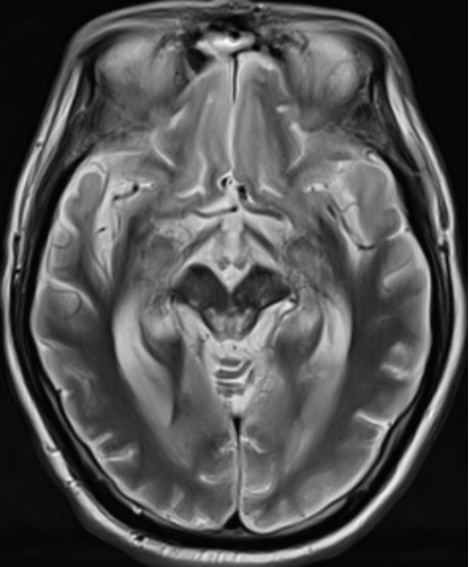

MRI病变评估方法参考既往研究中描述的方案[7]。由两位具有丰富经验的神经放射学家,在未知患者临床诊断的前提下评估双侧大脑区域病变情况,包括额叶、颞叶、顶叶、枕叶、胼胝体膝部和(或)体部、胼胝体压部、基底节区、丘脑、脑干、小脑,共计18个解剖区域。每个脑区采用二分类评分法:0分表示无病变或只有小的局灶性病变;1分表示有较大的病变(累及该脑区体积的30%以上)或弥漫性病变(图1)。

Figure 1. The T2-weighted and diffusion images of a patient

1. 一名患者的T2加权和弥散图像

患者为60岁男性,入院诊断为呼吸心跳骤停(心肺复苏术后)、脑梗死恢复期,入院时双侧瞳孔对光反射消失,图像显示两侧基底节区、丘脑弥漫性缺氧损伤,且脑干出现多发病变,患者出院时仍为植物状态。